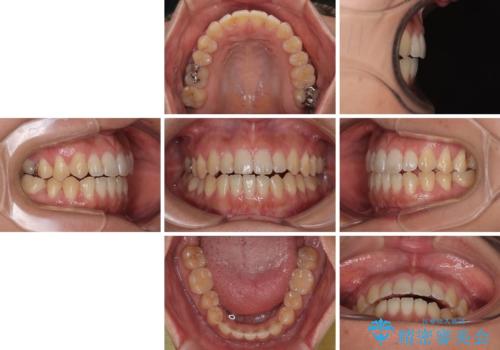

- 極端な開咬を気にして来院された患者様です。

開咬の方の特徴として、幼少期の指しゃぶりの癖や、強い舌の突出癖が挙げられます。

こちらの患者様も強い舌の突出癖が認められたため、矯正治療を行うにあたり、舌のトレーニングをしっかりと行っていただくように指示をいたしました。

開咬はインビザラインが得意とする歯列不正であるため、舌のトレーニングを行いながら、インビザラインにて矯正治療を行うこととしました。

担当医としては、もっと上下の前歯を接触させるところまで治療を進めたいという思いがありますが、今まで咀嚼できなかったものが食べられるようになったということで、この状態で治療終了となりました。